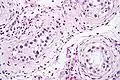

GCNIS is not palpable, and not visible on macroscopic examination of testicular tissue. Microscopic examination of affected testicular tissue most commonly shows germ cells with enlarged hyperchromatic nuclei with prominent nucleoli and clear cytoplasm. These cells are typically arranged along the basement membrane of the tubule, and mitotic figures are frequently seen. The sertoli cells are pushed toward the lumen by the neoplastic germ cells, and spermatogenesis is almost always absent in the affected tubules. Pagetoid spread of GCNIS into the rete testis is common. Immunostaining with placental alkaline phosphatase (PLAP) highlights GCNIS cell membranes in 95 percent of cases. OCT3/4 is a sensitive and specific nuclear stain of GCNIS.[3]

ITGCN. H&E stain.

ITGCN. H&E stain.